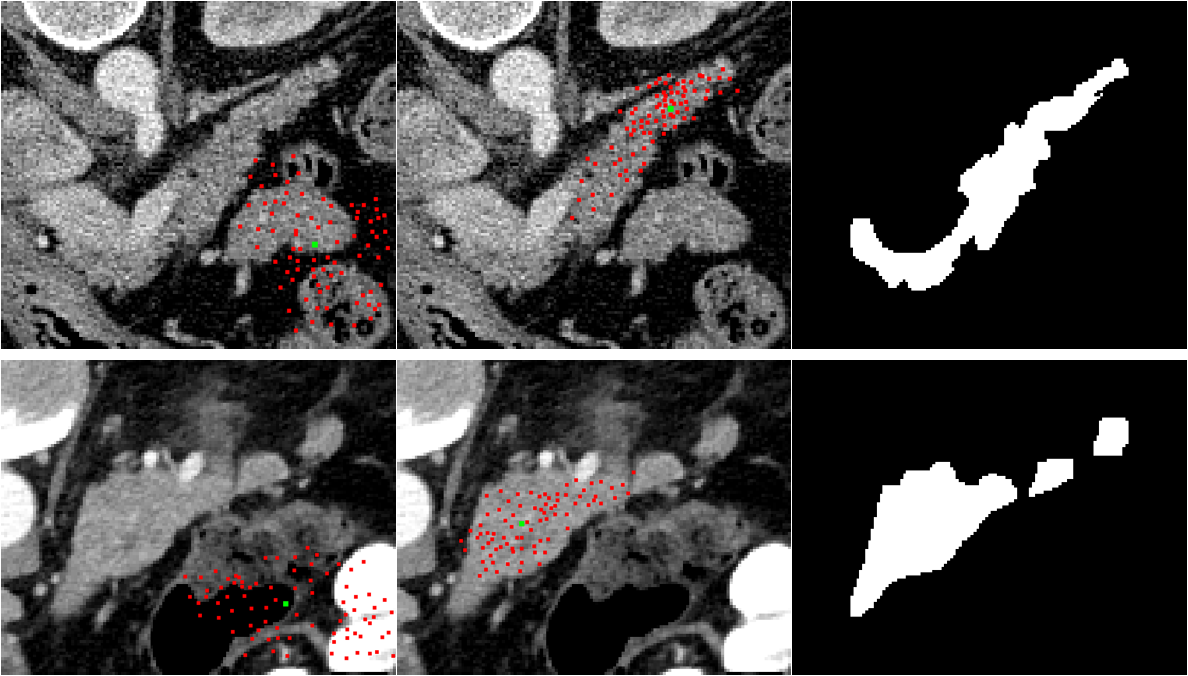

Refer to caption

Figure 5: Visualization of our deformable kernel. Each row is a test case in the segmentation phase. The images from left to right are offset kernel for background activation point, offset kernel for pancreas activation point and ground truth mask, respectively. Green dots are activation points, and red dots represent the receptive field of that activation point.

Generally speaking, the offset map is obtained by adding a convolutional layer after the last feature map. For every pixel in the feature map, two offsets are related to it, each for one axis. After shifting the coordinate of convolutional kernel, the feature is extracted by performing the convolution operation. The deformable kernel is exemplified in Fig.5.